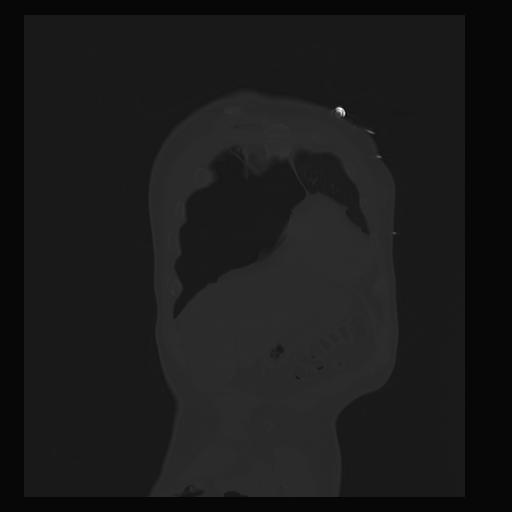

32 PULMON,CE,Coronal,3.000,PULMON,Coronal,